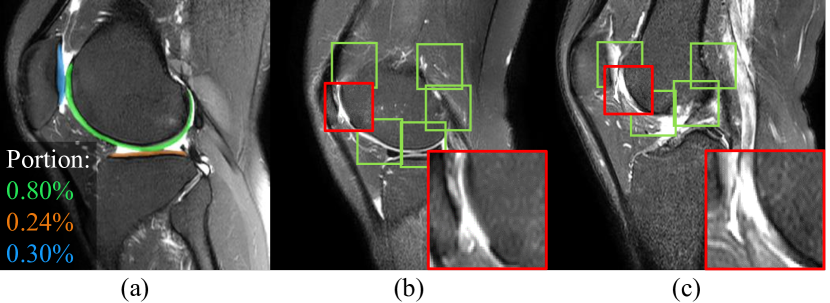

Refer to caption

Figure 1: There are many challenges for deep networks to assess knee cartilage defects: (a) Information Dilution: the cartilages (labeled in colors) occupy only a small portion of voxels, compared to the large background, in knee MRIs; (b-c) Structure Disidentification: along with the curved cartilage, the local appearance of individual patches can be highly confusing to determine whether the patches contain defects. For example, (b) and (c) both show the discontinuity of femoral cartilages. However, (b) is the femoral cartilage with a serious defect, and (c) is normal at the end zone of the femoral cartilage.

Information Dilution. For the subject-based and slice-based methods, they introduce large background into computation, which dilutes the portion of cartilage information. Knee cartilages are typically thin layers covering the heads of bones. As shown in Fig. 1(a), only a very small portion of voxels in the form of curved shapes, other than the large background in knee MRI, should be focused in cartilage defect assessment. However, in conventional CNNs, the receptive field cannot be easily adjusted following the size and the shape of the target anatomy.

Structure Disidentification. Patch-based methods reduce the irrelevant background by cropping patches along the cartilage. But the global shape information of knee cartilages is dropped out, too. In addition, the local appearance of individual patches at different positions of the cartilages is also highly diverse. We show patches with similar local appearance in Fig. 1(b) and (c). Although (b) and (c) both have discontinuity of femoral cartilages, (b) indicates the femoral cartilage defect, and (c) is normal at the end zone of the femoral cartilage. Such confusion in local appearance can decrease the capability of patch-based methods in finding cartilage defects.